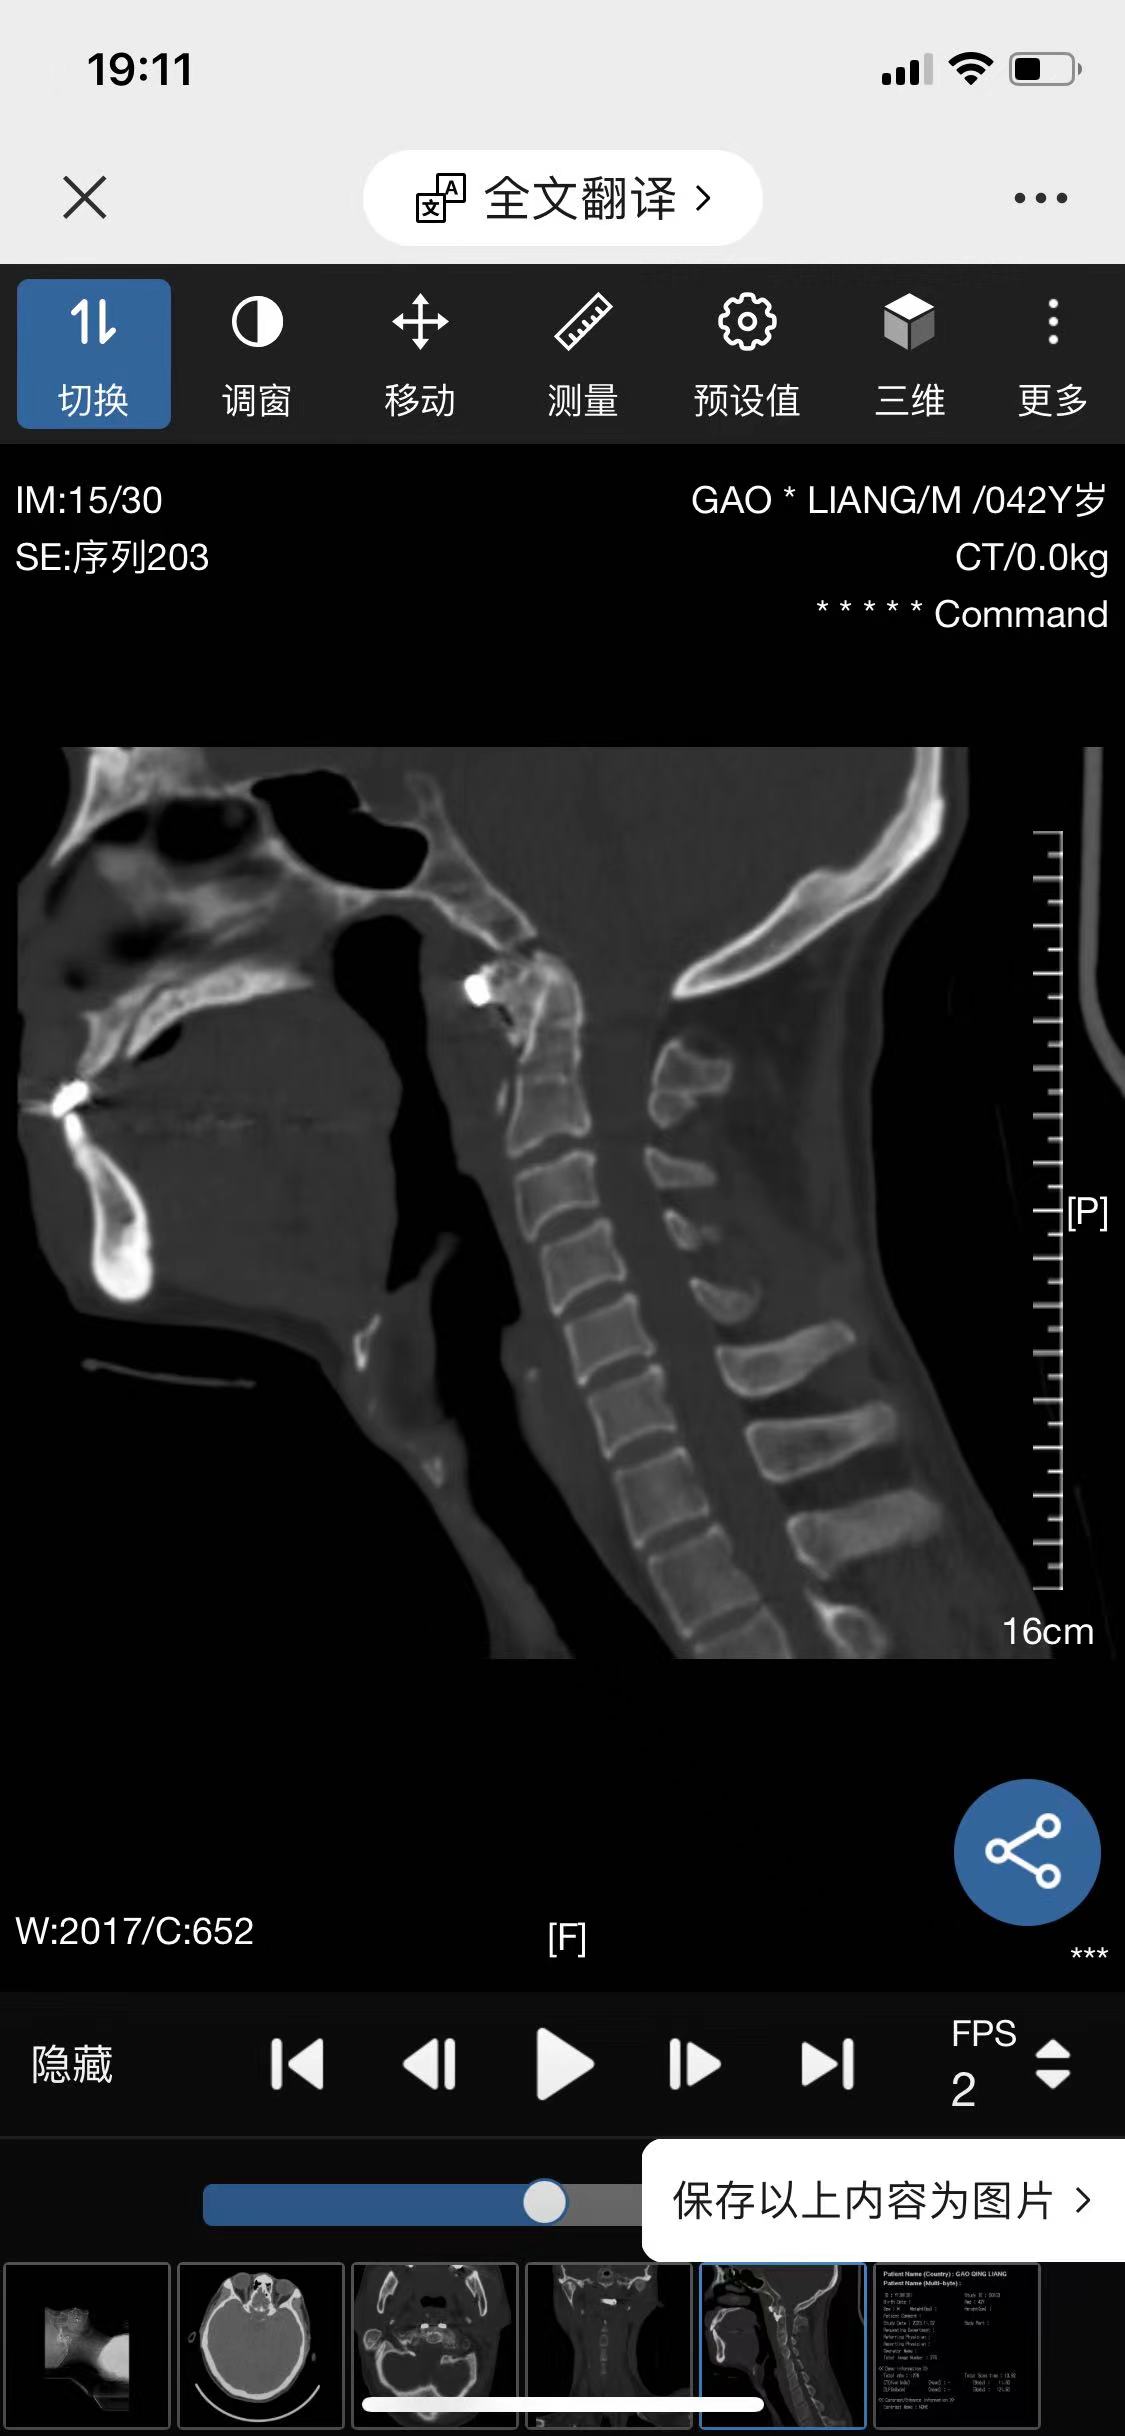

• 诊断:寰枢椎脱位

• 影像:

• 术后影像: